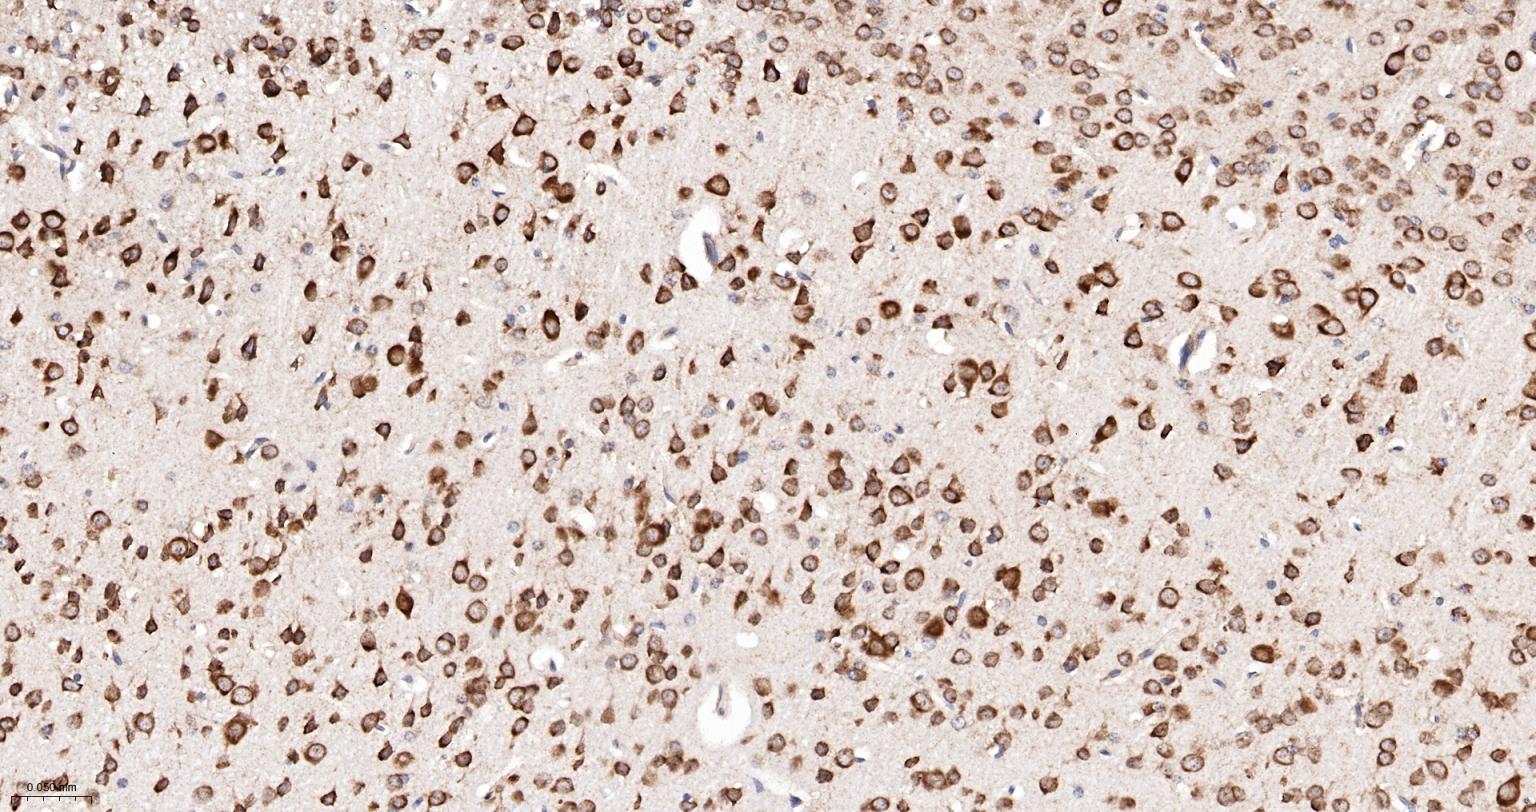

Paraformaldehyde-fixed, paraffin embedded Human Cerebrum; Antigen retrieval by boiling in sodium citrate buffer (pH6.0) for 15 min; The section was incubated with MAP3K2 Monoclonal Antibody, Unconjugated (bsm-61285R) at 1:200 overnight at 4°C, followed by conjugation to the bs-0295G-HRP and DAB (C-0010) staining.

Paraformaldehyde-fixed, paraffin embedded Rat Cerebrum; Antigen retrieval by boiling in sodium citrate buffer (pH6.0) for 15 min; The section was incubated with MAP3K2 Monoclonal Antibody, Unconjugated (bsm-61285R) at 1:200 overnight at 4°C, followed by conjugation to the bs-0295G-HRP and DAB (C-0010) staining.

Paraformaldehyde-fixed, paraffin embedded Mouse Cerebrum; Antigen retrieval by boiling in sodium citrate buffer (pH6.0) for 15 min; The section was incubated with MAP3K2 Monoclonal Antibody, Unconjugated (bsm-61285R) at 1:200 overnight at 4°C, followed by conjugation to the bs-0295G-HRP and DAB (C-0010) staining.